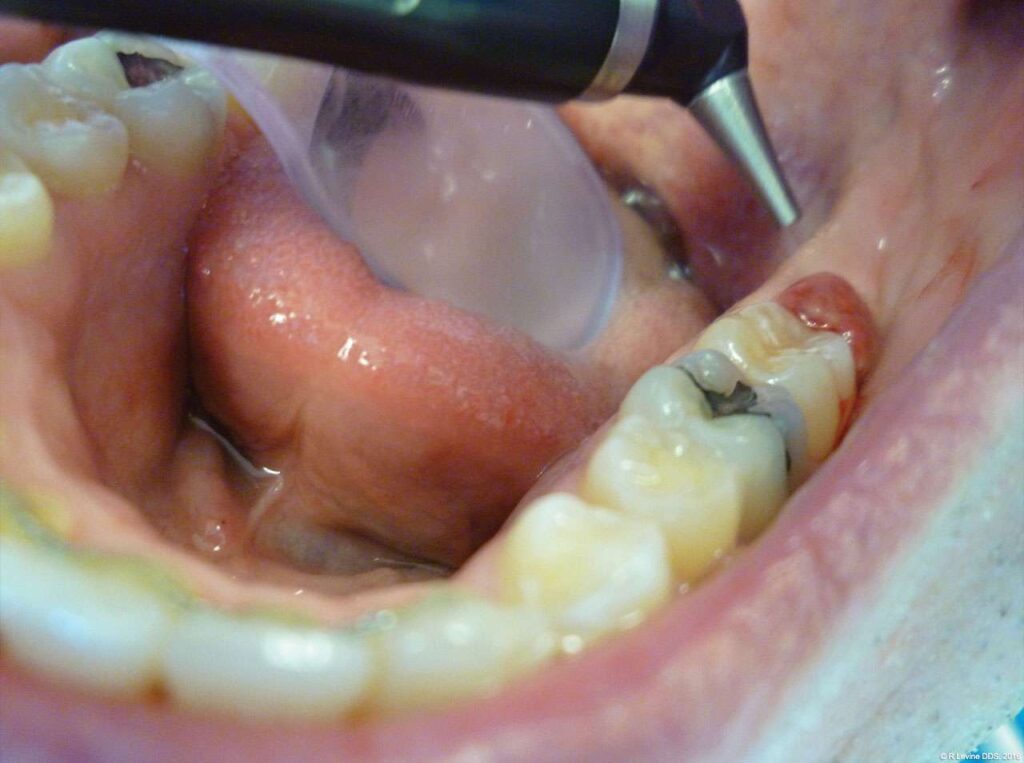

For ablation of the inflamed tissue, the laser was set to 4 W in the SuperPulse mode with repeat pulsing at a 25 millisecond pulse-width and 29 Hz repetition rate. The tipless dental handpiece was used at a 3 mm to 5 mm nozzle-to-tissue distance.

- The angled handpiece of the CO2 laser was held perpendicular to the target lesion (Figure 4) and the ablation of the inflamed tissue began (Figure 5). The dental surgeon was careful to avoid contact between the laser beam and the tooth enamel. (Note: In this case, the inflamed tissue was located distally from the involved molar. There was no direct contact of the beam with the tooth, as the surgeon was careful not to hit the enamel. However, if an operculum covers part of the tooth, an adaptive tool (for example, a wax spatula) needs to be inserted between the tissue and the tooth to prevent possible damage. For an inexperienced CO2 laser surgeon, it is important and highly recommended to always shield the tooth during the procedure.[6])

- After the initial pass with the laser, the inflamed gingiva bled slightly and the surgeon defocused the beam by increasing the nozzle-to-tissue distance to quickly obtain hemostasis (Figure 6). Note the excellent visualization and the clear operatory field.